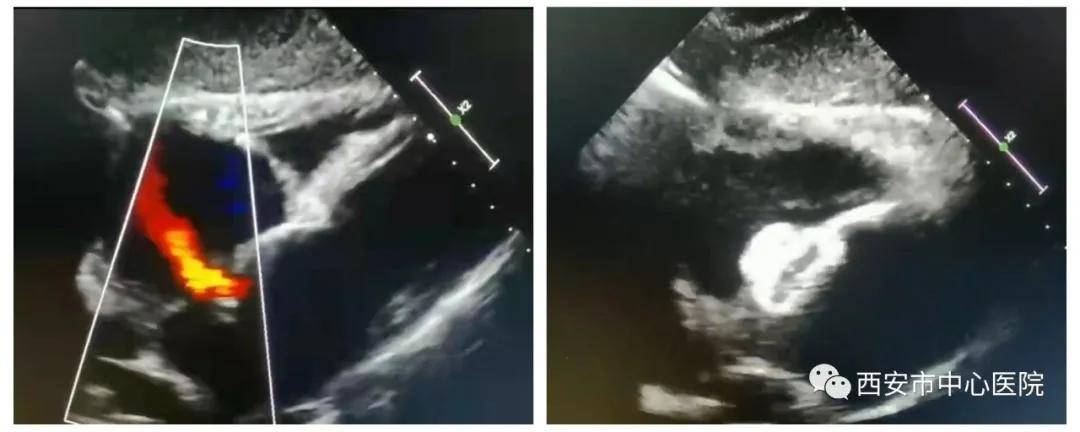

近日 , 市中心医院心内科马锋主任团队成功为一先天性心脏病房间隔缺损合并心房颤动的患者实施了房间隔缺损+左心耳联合封堵术 , 手术顺利 , 手术效果满意 。

【手术|一箭双雕——西安市中心医院心内科成功实施微创房间隔缺损+左心耳联合封堵术】该患者为一66岁老年女性 , 30多岁时发现先天性心脏病房间隔缺损 , 一直不敢手术 。 近些年出现房颤 , 胸闷、气短症状明显 , 间断心慌、头痛发作 , 口唇发绀 , 严重影响生活质量 , 经朋友介绍于西安市中心医院住院治疗 。 入院检查后发现病人心房扩大 , 肺动脉高压 。 马锋主任对患者进行了全面评估 , 综合考虑后制定了同时行房间隔缺损+左心耳联合封堵术的方案 , 用一根鞘管经过缺损的房间隔完成两个封堵 , 在修补心脏结构缺损的同时降低房颤血栓风险 。 在超声医学科郑瑜主任及麻醉科崔晓岗主任的协作下 , 马锋主任与潘军强副主任医师成功实施手术 。 术后患者自觉症状明显改善 , 头痛缓解 , 胸闷气短减轻 , 口唇转红润 。 患者现病情平稳 , 拟于近期出院 。

此次联合手术的成功实施 , 标志着心内科在复杂心血管疾病的介入诊疗方面迈上了新台阶 。 心内科将继续深入发展心血管微创介入诊疗技术 , 尤其把心血管新技术、新业务及复杂心血管疾病的诊疗作为发展重点 , 促进科室整体发展 , 更好服务广大心血管疾病患者 。